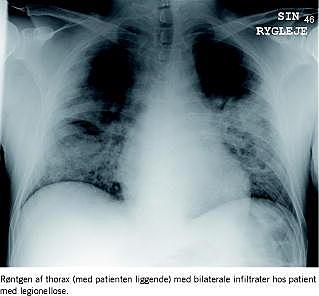

En 48-årig mand, der havde været i behandling med infliximab hver anden måned igennem de seneste tre år for svær psoriasis, indlagdes akut efter syv dage med feber, tør hoste, tiltagende åndenød, hovedpine, kvalme, ublodig diare og tiltagende cerebral konfusion. Computertomografi af cerebrum samt undersøgelse af spinalvæsken var normale. Røntgen af thorax påviste udbredte bilaterale infiltrater, arterieblodsundersøgelse viste hypoksi, og patienten blev startet i intravenøs behandling med penicillin og klarithromycin. Patienten blev efterhånden respiratorisk udtrættet og overflyttedes på anden indlæggelsesdag til en intensiv terapiafdeling til respiratorbehandling. Bloddyrkning var uden vækst. Da der endnu ikke var diagnostisk afklaring, tillagdes behandling med rifampicin og højdosis-trimetroprim/sulfametoxazole. På tredjedagen kom der positivt svar på urin-legionella-antigen samt positiv polymerasekædereaktion (PCR) for Legionella pneumophila i bronkialskyllevæske. Behandlingen fortsattes herefter med klarithromycin og rifampicin gennem i alt 21 dage. Efter 12 dage var patienten på spontan respiration med normal iltsaturation og aftagende infiltrater ifølge røntgen af thorax, hvorefter patienten hurtigt restituerede.